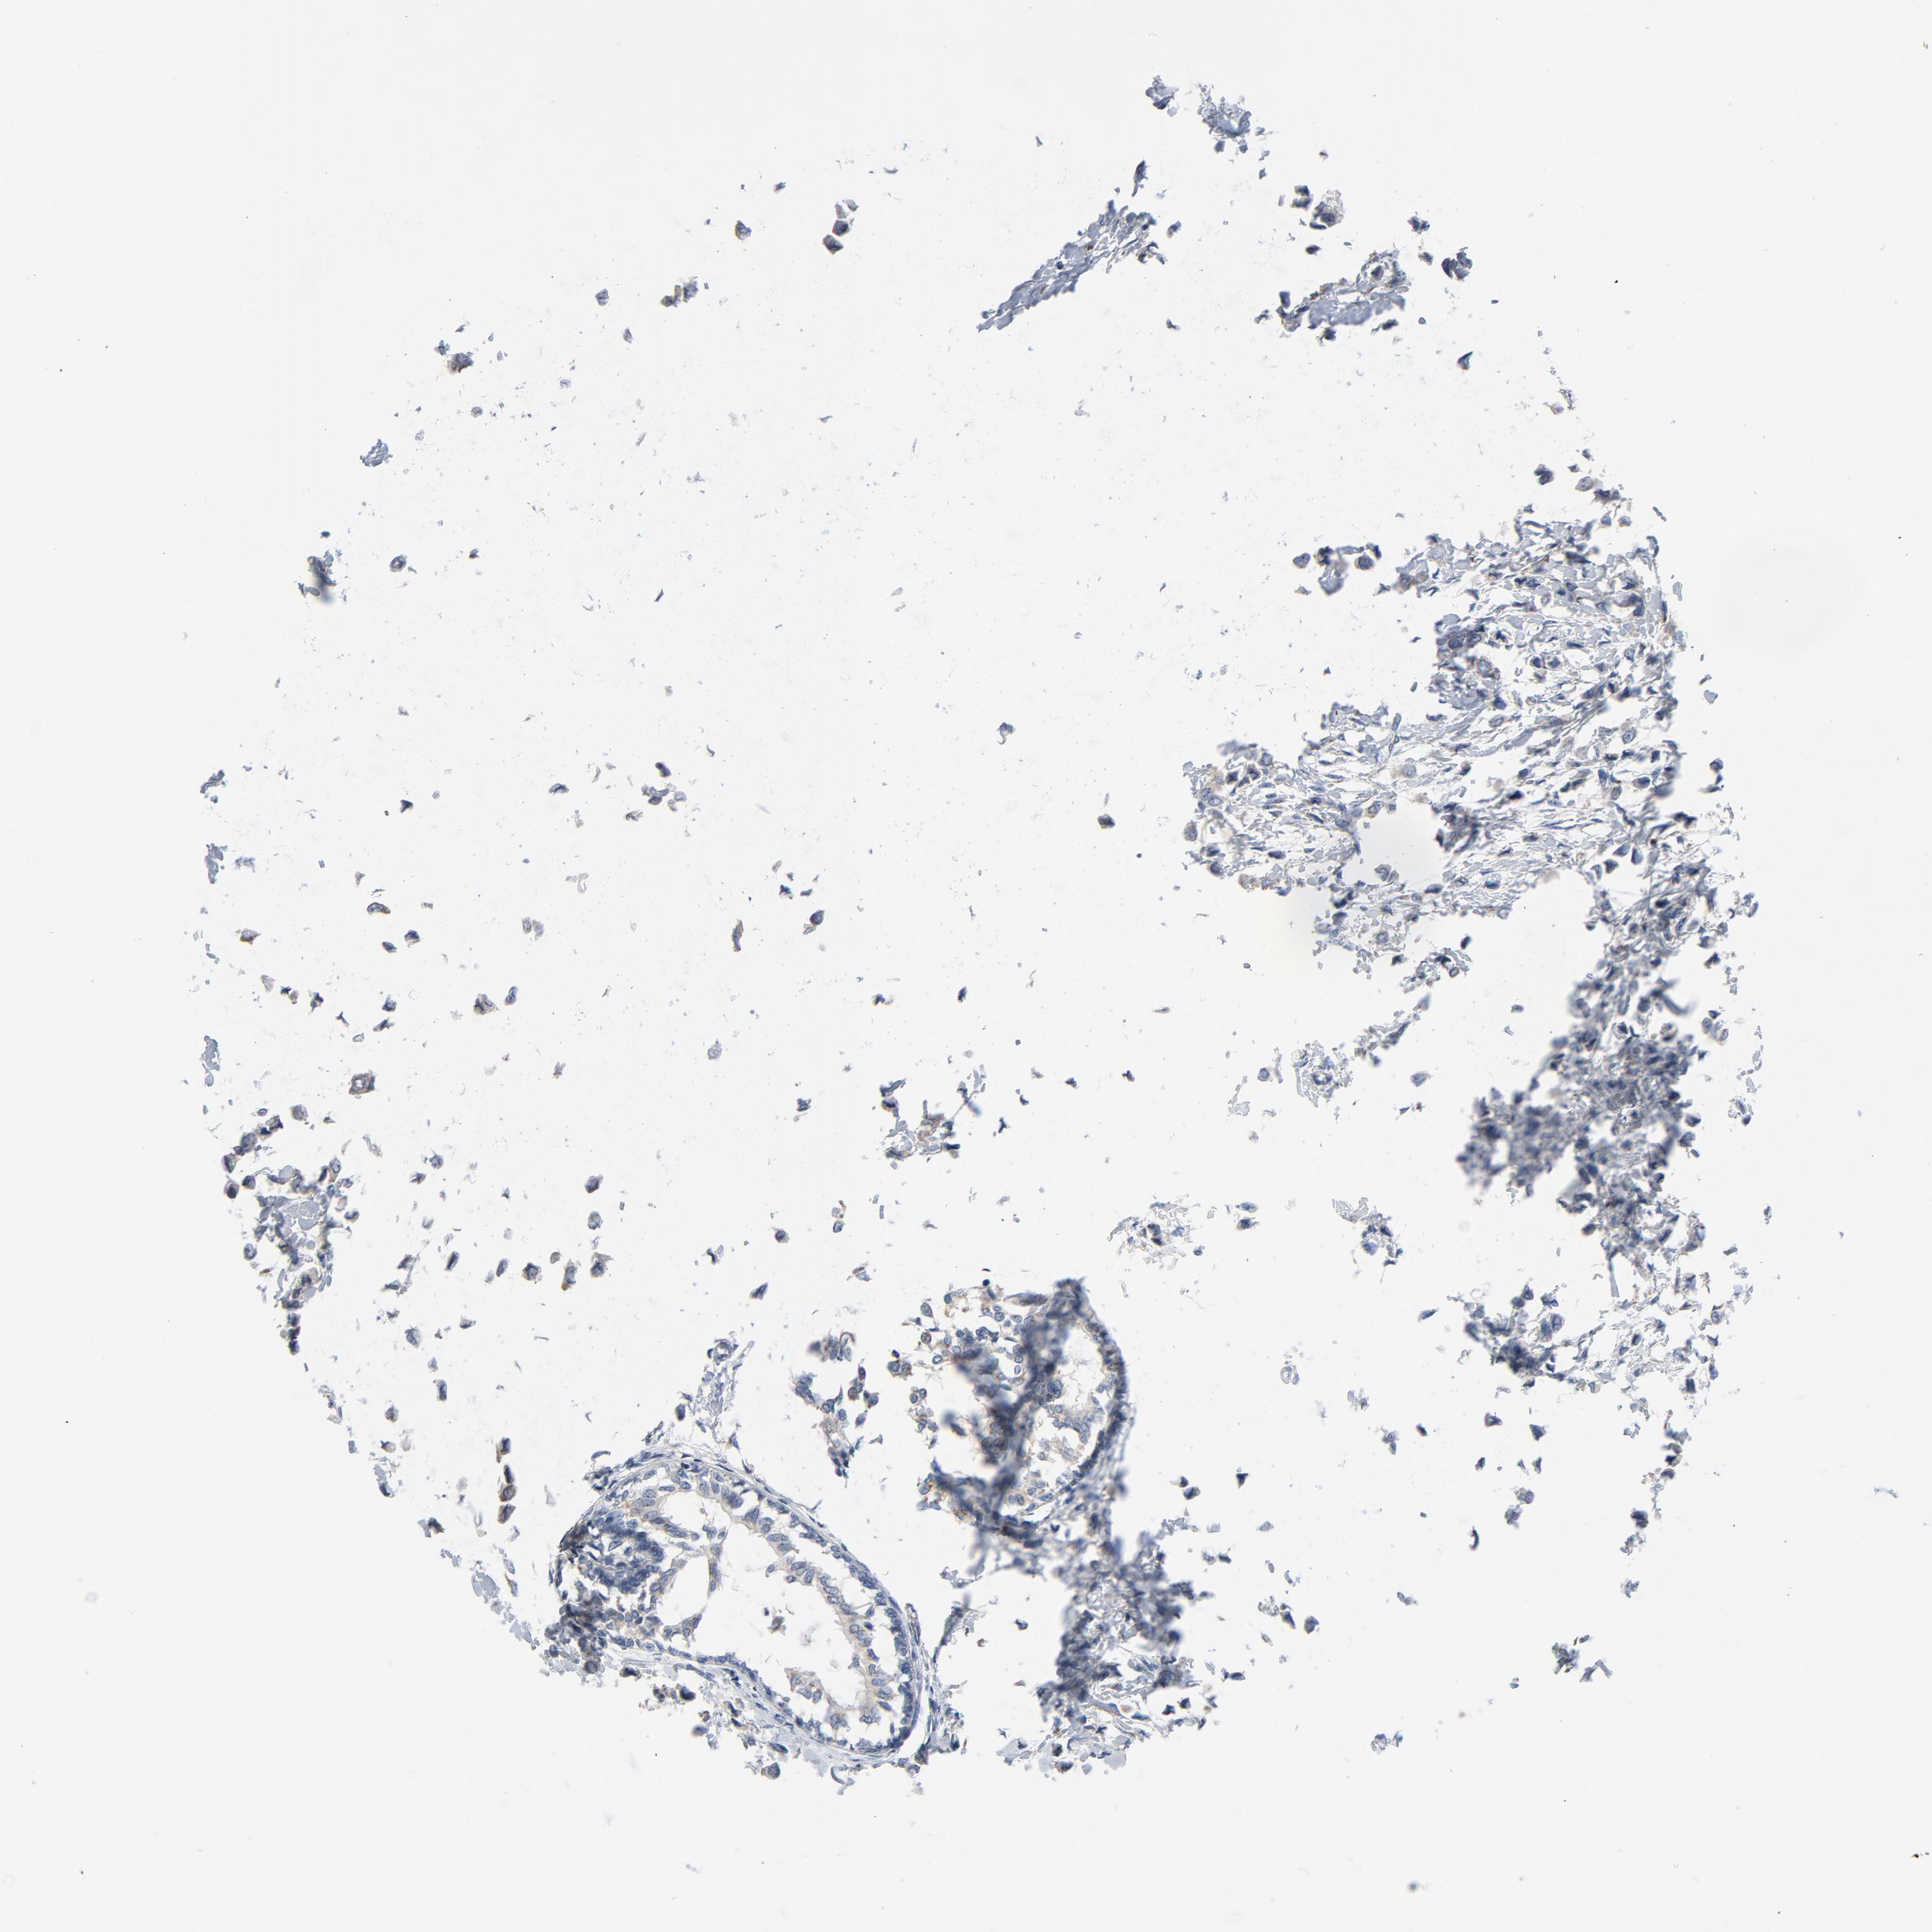

BRCA TCGA BRCA VALIDATION PROTEIN EXPRESSION

Breast cancer

Human cancer

Breast invasive carcinoma